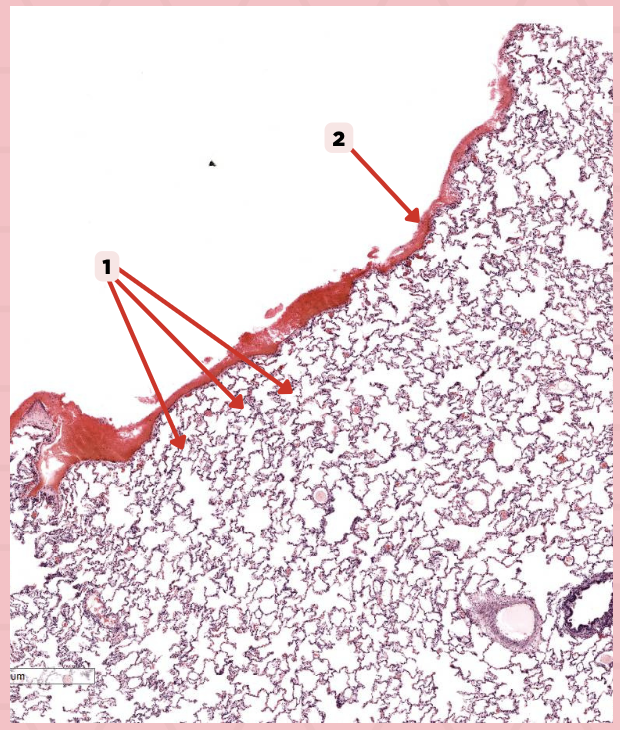

Simple squamous epithelium (Mesothelium)

The surface related to the pleural cavity is in line with what type of epithelium?

Lumens and Interalveolar septa

Name the irregular spaces and the fine threads of tissue that separate them.

Visceral pleura

Identify the structure labeled as 1.

Alveoli

Visceral Pleura

What type of pleura is a thin layer of connective tissues that borders on the outside by mesothelium?

Simple Squamous Epithelium

What epithelium lines the red arrow?

Mesothelium

Identify the structure labeled as 1.

Pulmonary Capillaries

Oxygenated blood is collected by structure #2 from what source/structure?